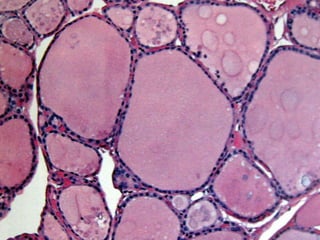

HISTOLOGIA DA

TIREÓIDE

• 13.

Os Hormônios folicularestireoideanos Tiroxina (t4) Triiodotironina (t3)